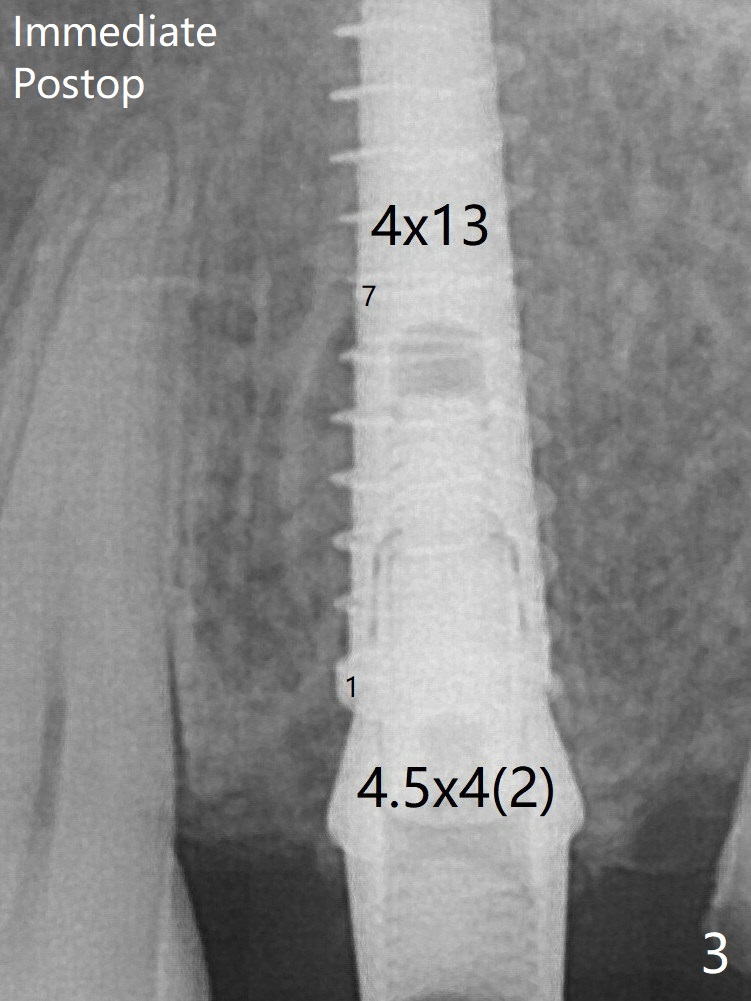

There is a gap mesial to the implant between the 1st and 7th threads immediate postop (Fig.3).  The gap is absent between 1st and 6th threads 8.5 months postop (Fig.5) with formation of the dense crestal bone.